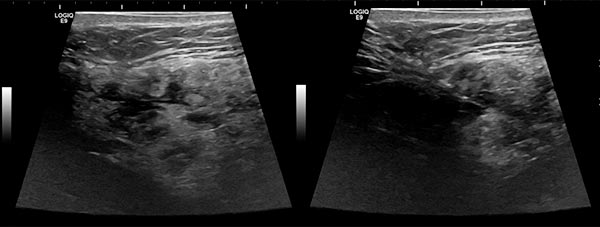

Ultrasound images (automatically assembled 2D B-mode images) before sclerotherapy. The initially hypoechoic cavities of the venous malformation are occluded by the inflammation induced by sclerotherapy.